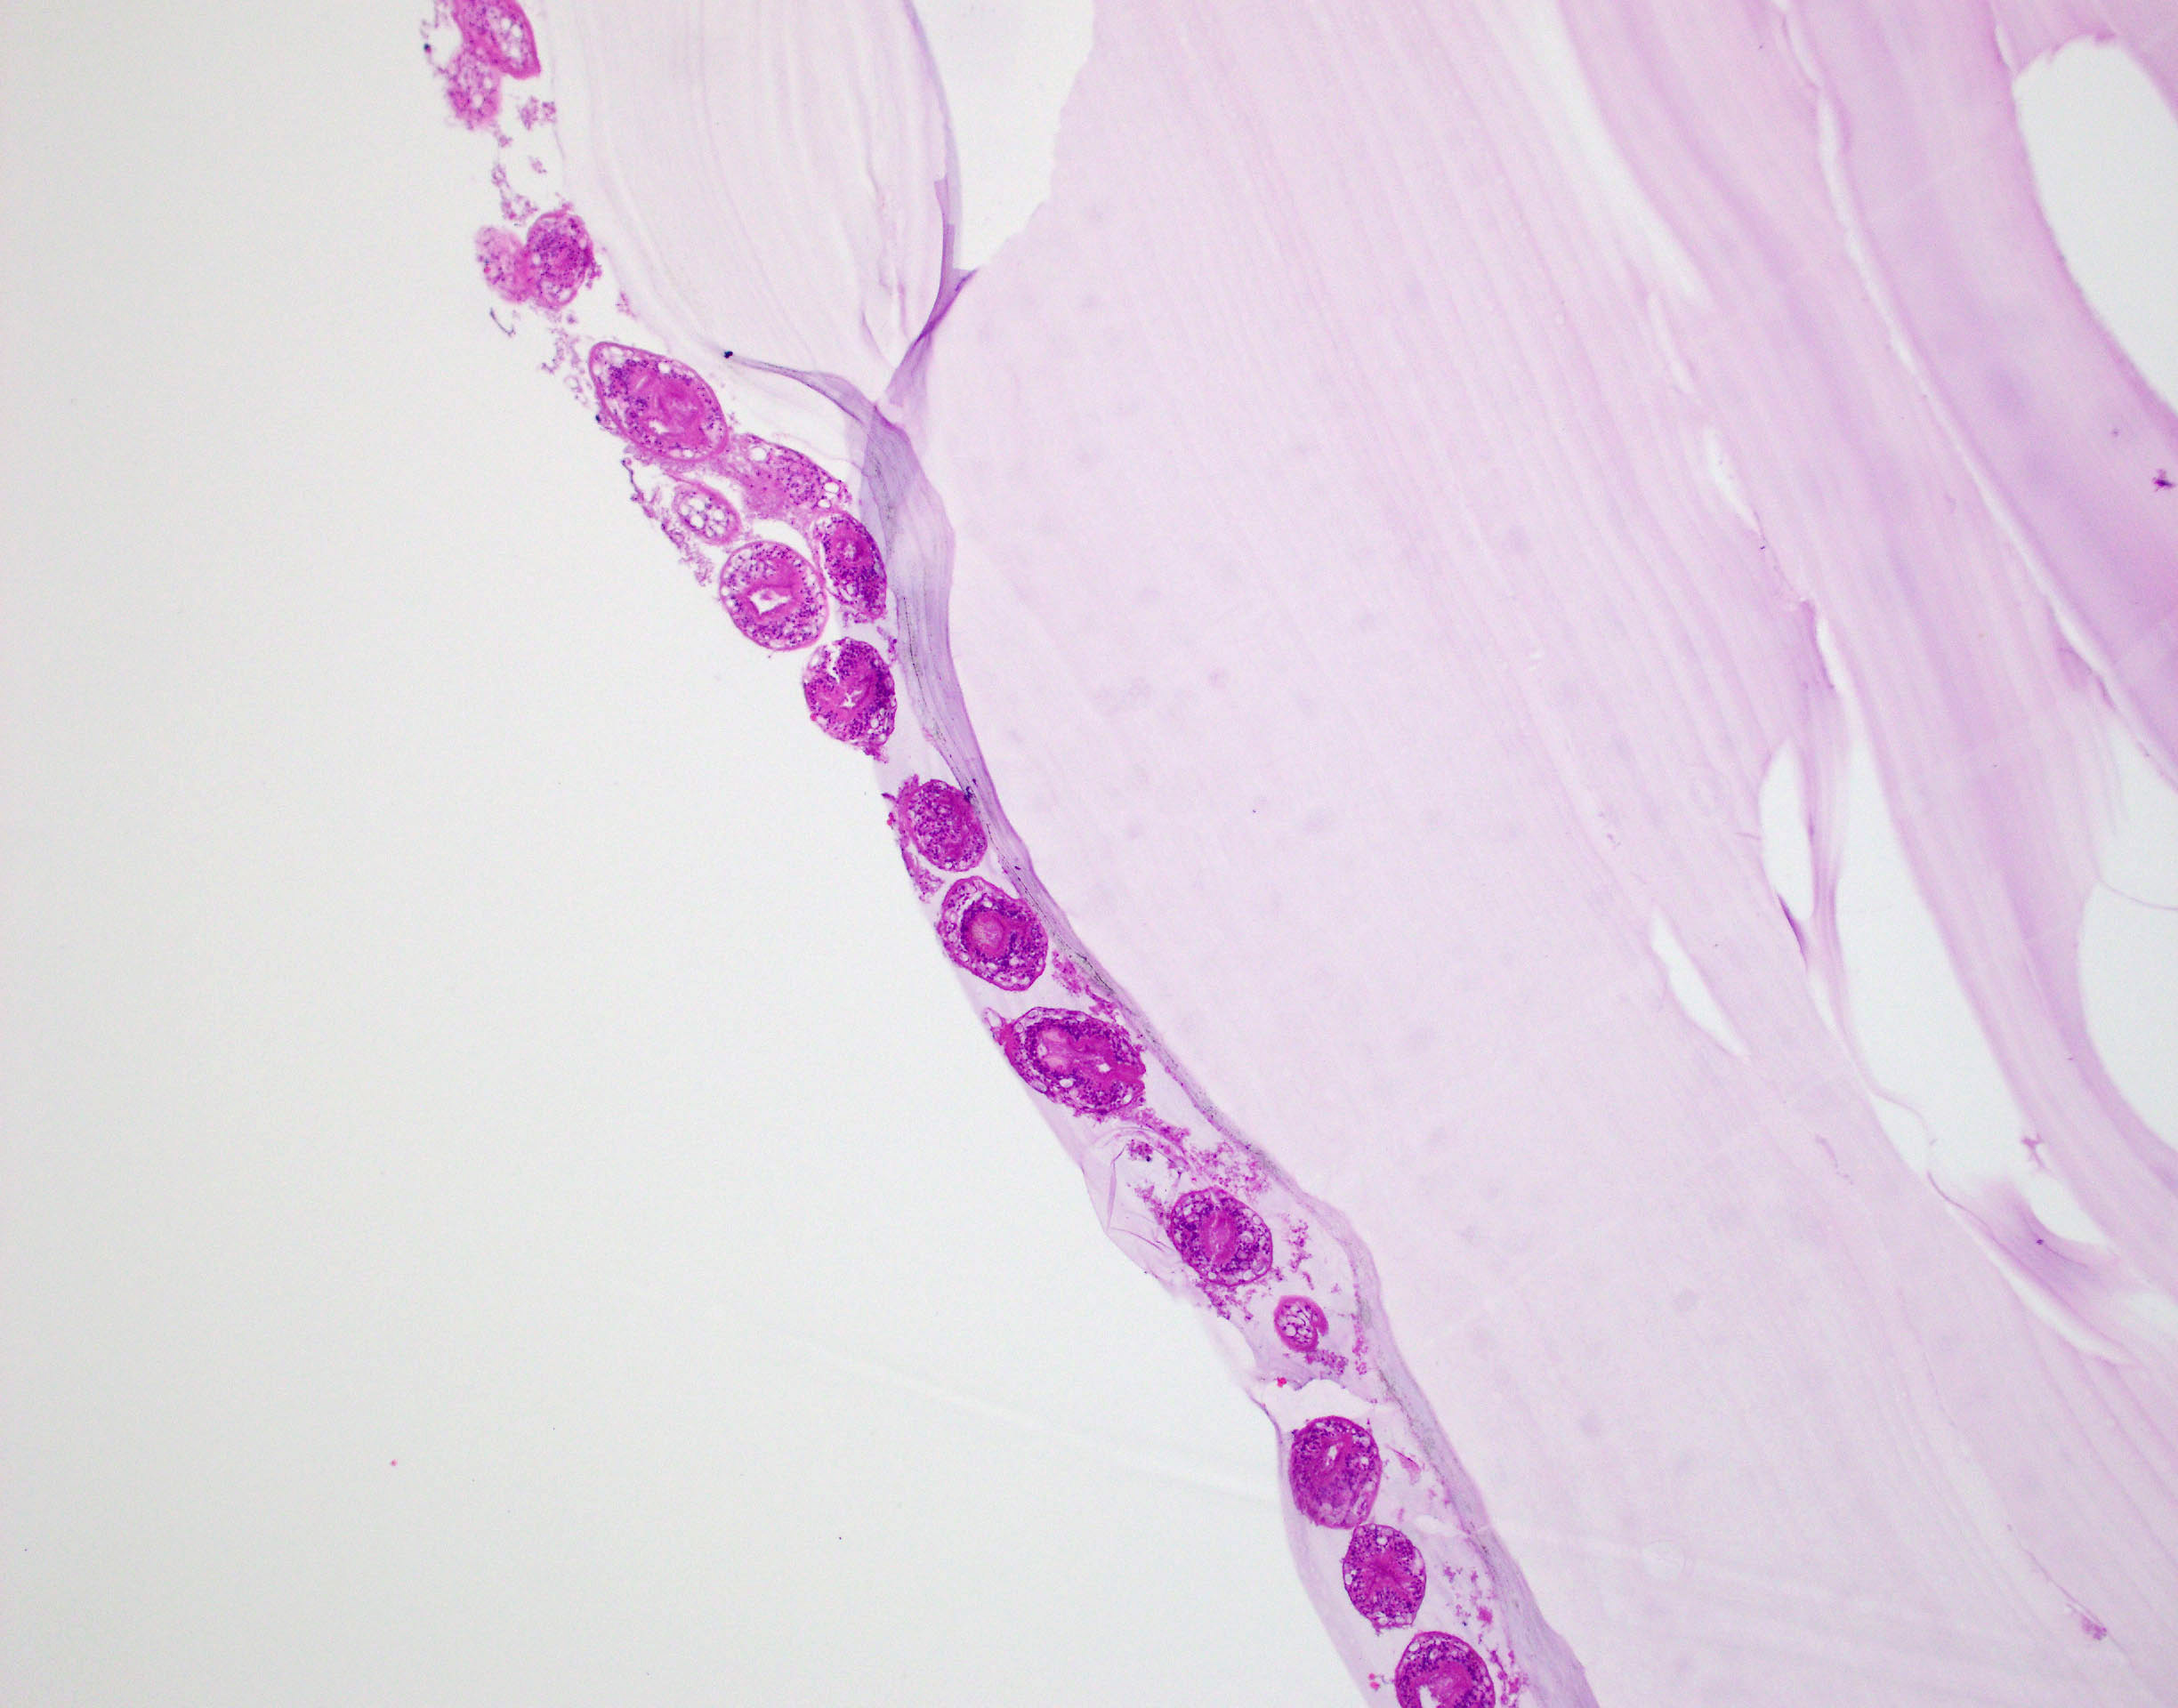

Microscopic (histologic) description

- E. granulosus

- Cyst wall has 3 structural components:

- Outer acellular laminated membrane (1 mm thick)

- Germinal membrane (a transparent nucleated lining)

- Protoscolices, attached to the membrane and budding from it

- Protoscolices are ovoid and contain hooklets (birefringent under polarized light) and a sucker

- Outer fibrotic layer with granulation tissue with increased eosinophils also exists

Microscopic (histologic) images